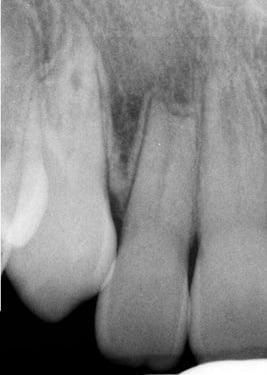

Lesión Endo-Perio Combinada

Una lesión endo-perio combinada es una condición en la que hay tanto una infección de la pulpa como una enfermedad periodontal.

Los pacientes pueden experimentar dolor, hinchazón y movilidad dental.

El tratamiento incluye tanto el tratamiento de conducto como el tratamiento periodontal para abordar ambas infecciones. La coordinación entre el endodoncista y el periodoncista es esencial.